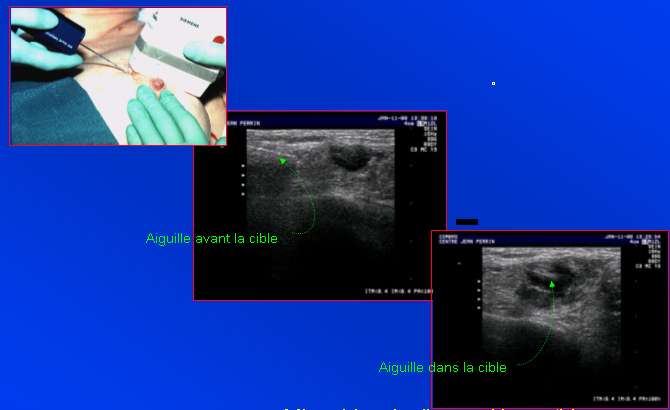

Mode de guidage. Abord oblique.

Micro-biopsie d’une adénopathie. L’ensemble de la course

de l’aiguille doit être vu